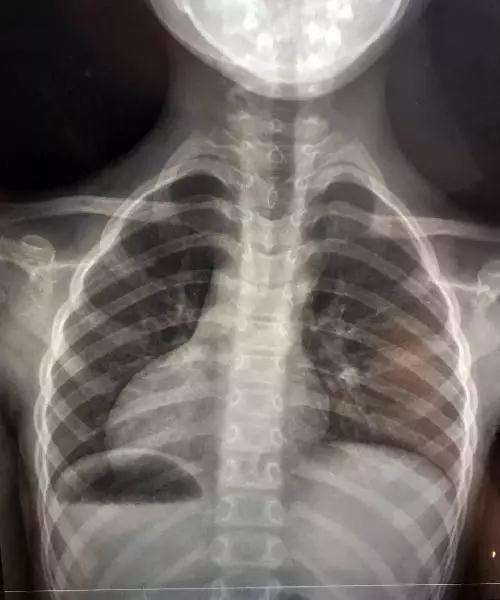

幸运的是,经过3天的观察等待,掉落到肚子里的针,最终,被胡女士女儿通过代谢排了出来。虽然结果是有惊无险,但是看着从女儿身体里取出的近5厘米长的工具针,胡女士的心情始终无法平复。